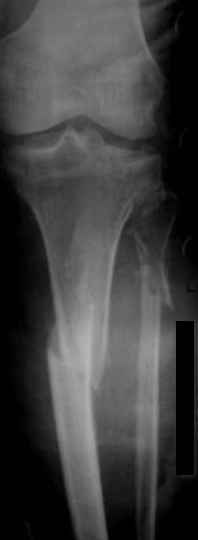

Мама 4 дня назад получила двойной перелом в голени

Диагноз такой:

1) Открытый перелом нижней 3-й большой берцовой кости

2) Верхней 3-й малой берцовой кости справа со смещением

Снимки смогли сделать только через 4 дня, я смогла приложить только 1 снимок к форуму

В пятку ей вставили штырь и повесили гирю сразу.

Есть возможность сделать операцию и вставить титановую пластину.

Проконсультировались с другим врачом-травматологом, он говорит, что при таком переломе нужен аппарат Илизарова. И делать нужно как можно скорее.

А наш врач говорит, что в ноге, так где кость проткнула кожу есть инфекция, сейчас ей обрабатывают марганцовкой и назначили кварцевание. Врач назначил операцию по вставлению тинановой пластины только через неделю, ссылаясь на инфекцию. Говорит, что если делать сейчас мы сможем ее занести внутрь на 80%, а он на себя такую ответственность брать не собирается. Говорит там пузырь и только когда кожу залечим, будем делать операцию

Другой врач говорит, что важно сделать операцию сейчас, а кожу залечить потом